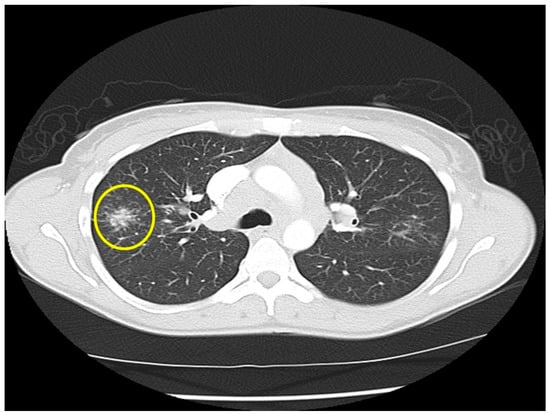

Figure 5.

Chest CT image of a “galaxy sign” in a patient with pulmonary sarcoidosis. Micronodules coalescence into a central mass-like lesion (within circle).